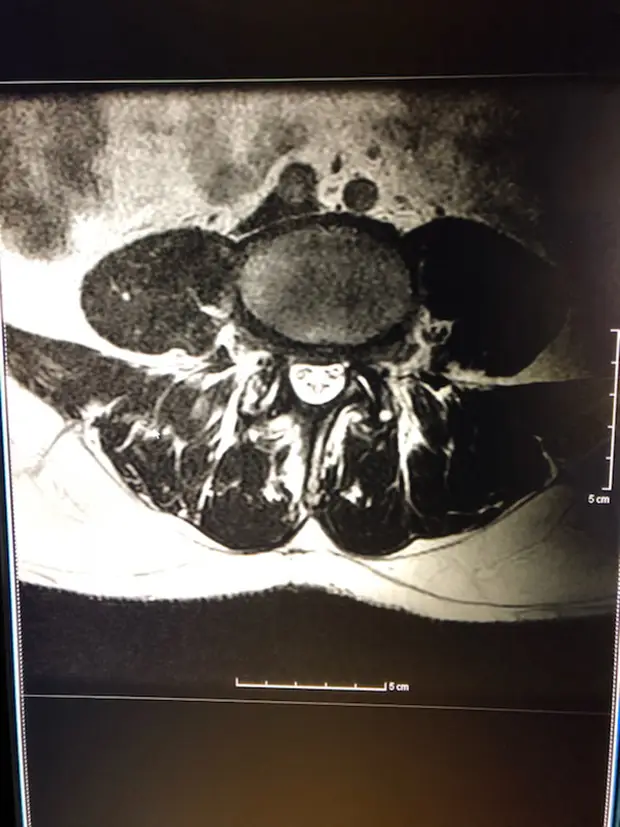

Take, for instance, the spinal stenosis of the lumbar spine. With age, the canal in which the spine and nerves lie becomes constricted due to stenosis and degeneration, such as bulging or herniated discs, bone spurs, or arthritis of the spine. This constriction compresses the nerves in the spinal column in the lower (lumbar) spine and makes walking difficult and uncomfortable.

The symptoms of this malady include pain, numbness, weakness, or tingling in the legs, especially after walking or standing for a long period of time. A typical presentation of this condition is that of an elderly person who is able to walk for a while, but begins to limp as the nerves get compressed and the legs become numb or start to tingle and feel weak. Sitting or lying down usually alleviates the tingling or numbness or weakness in the legs because spinal canal opens up enough that the nerves are less compressed. As time goes on, the distance the person can walk becomes shorter and the breaks to relieve the discomfort become longer.

“The majority of people benefit from surgery,” explains Dr. Emilio Nardone, a neurosurgeon at Central Illinois Neuro Health Sciences in Bloomington. However, the traditional procedure to resolve neurogenic claudication, called decompressive laminectomy, involves removing some of the backbone as well as moving muscle, tendons, and other thickened tissue to open up the canal that the nerves run through, making it less constrictive and thus relieving the discomfort.

More recently, a minimally invasive procedure has been developed that not only opens up the canal, but also is less damaging to the bone and soft tissue surrounding the spine. This technique, called a minimally invasive bilateral lumbar decompression with a unilateral approach, offers several advantages.